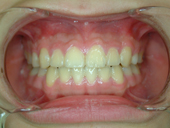

圖三、門牙暴牙及大牙縫

圖四、矯正後,牙縫關閉

導致牙齒排列不整的原因包羅萬象,情況也是千奇百怪。有的人是因為牙齒大小和牙床大小不諧調,導致齒列擁擠(圖一、二)或是產生縫隙,台灣人最介意的“牙齒漏財”即屬於縫隙這個類型(圖三、四);有的人則是牙齒長到不該長的位置而沒有冒出牙床(圖五、六);有些人則是上下顎骨發育不諧調,導致戽斗(或稱月亮臉)或是鳥臉的狀況;除此之外,暴牙、先天缺牙、多生牙、後天蛀牙或長期缺牙導致相鄰牙齒東倒西歪、車禍外傷導致牙齒移位或喪失牙齒(圖七、八)、牙周病所導致的門牙散開…等等,都是齒顎矯正的適應症。